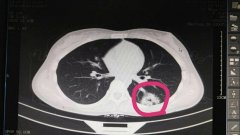

日前,我院急診科接到120通知,接回一車(chē)禍病人,入院時(shí)表述胸腹部疼痛,并呈現出血壓下降……